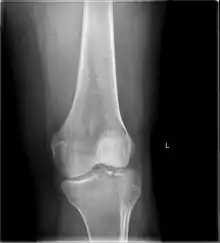

Tibial plateau fracture

Other namesFractures of the tibial plateau

A severe tibial plateau fracture with an associated fibular head fracture

A tibial plateau fracture is a break of the upper part of the tibia (shinbone) that involves the knee joint.[1] Symptoms include pain, swelling, and a decreased ability to move the knee.[1] People are generally unable to walk.[2] Complication may include injury to the artery or nerve, arthritis, and compartment syndrome.[1]